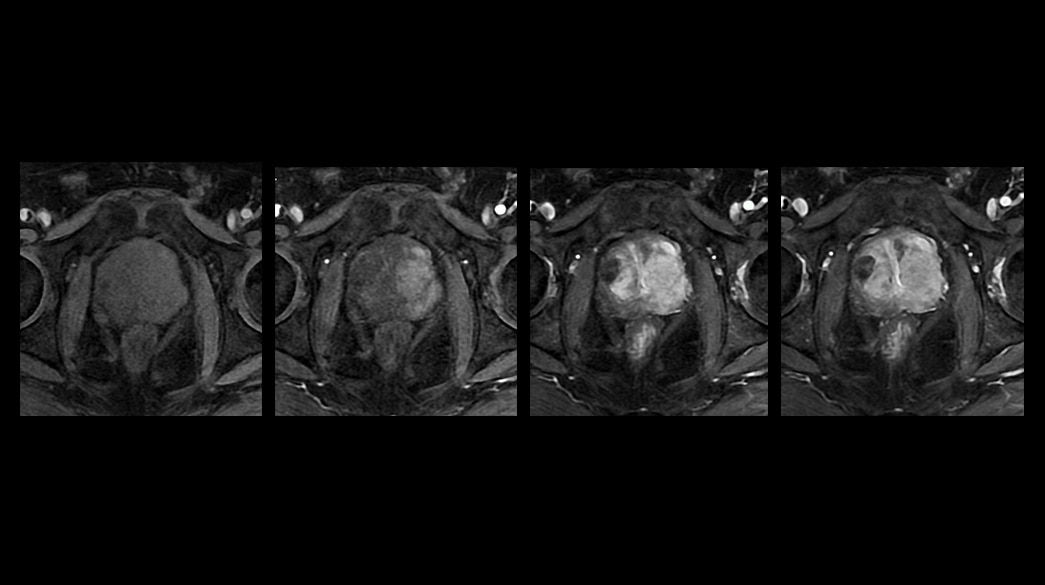

Quantifiable

Provides quantitative and actionable information

Consistent

Motion and distortion-reduced scans with high-resolution and contrast